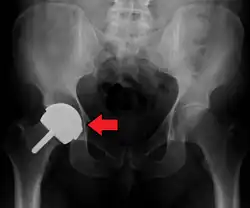

Hemiarthroplasty

Hemiarthroplasty is a surgical procedure that replaces one half of the joint with an artificial surface and leaves the other part unchanged. This class of procedure is most commonly performed on the hip after an intracapsular fracture of the femur neck (hip fracture). The procedure is performed by removing the head of the femur and replacing it with a metal or composite prosthesis. The most commonly used prosthesis designs are the Austin Moore and Thompson prostheses. A composite of metal and high-density polyethylene that forms two interphases (bipolar prosthesis) can be used. The monopolar prosthesis has not been shown to offer any advantage over bipolar designs. The procedure is recommended only for elderly/frail patients, due to their lower life expectancy and activity level. This is because over time the prosthesis tends to loosen or to erode the acetabulum.[101] Independently mobile older adults with hip fractures may benefit from a total hip replacement instead of hemiarthroplasty.[102]

Hip prosthesis for hemiarthroplasty. This example is bipolar, meaning that the head has two separate articulations. -

X-ray of the hips, with a right-sided hemiarthroplasty